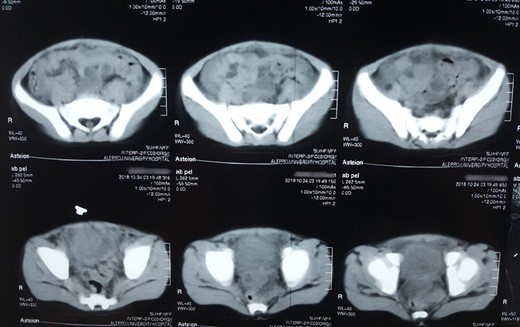

Non-contrast abdominal computed tomography (non-contrast CT) demonstrated a high-density midline mass above the bladder (Fig. 3).

Abdominal non-contrast CT scan showed hyperdensity mass above the bladder.